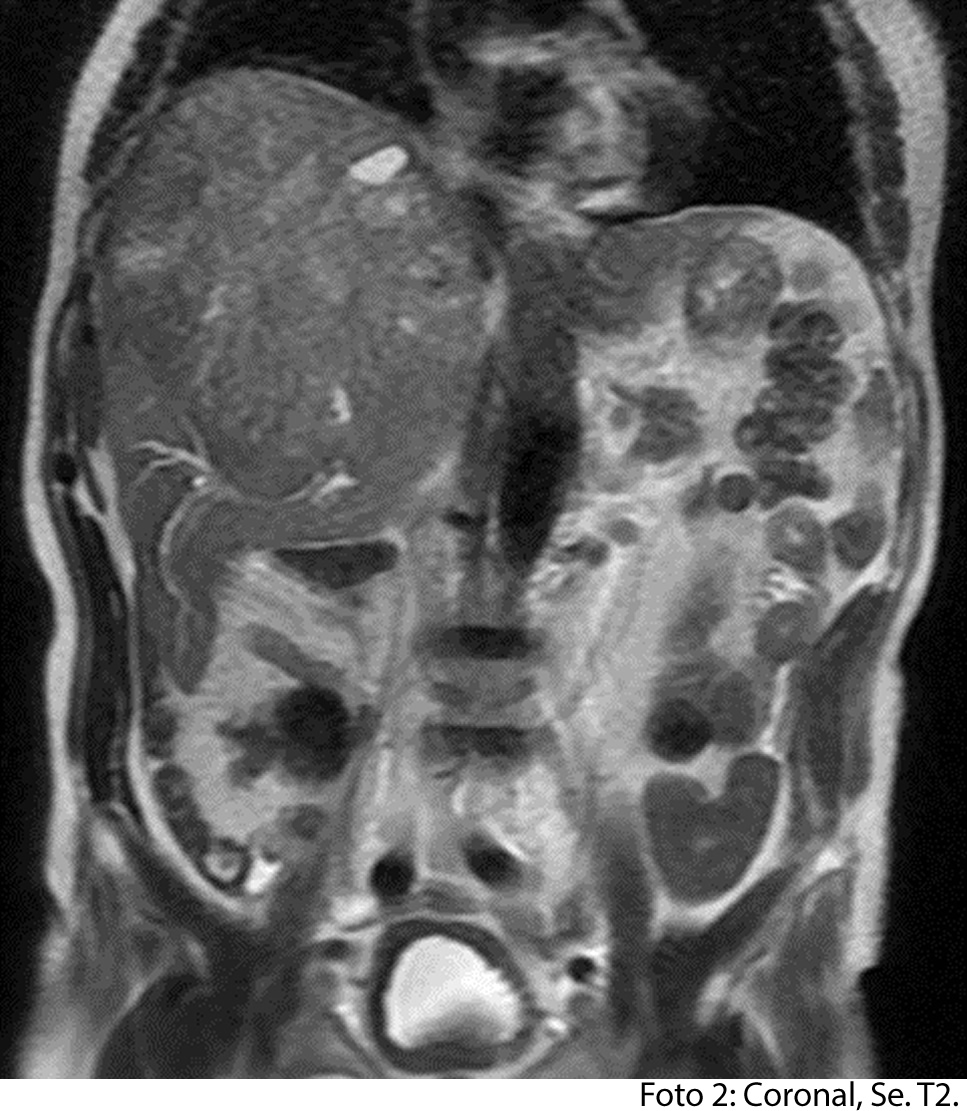

HALLAZGOS IMAGENOLOGICOS

• HEPATOCARCINOMA FIBROLAMINAL QUE COMPROMETE TODO EL LÓBULO DERECHO DEL HÍGADO

Síntomas: Dolor en hipocondrio derecho y/o en epigastrio. Debilidad y pérdida de peso. Hiporexia, saciedad temprana y llenura postprandial. Aumento de volumen abdominal y aparición de masa en hemiabdomen superior. Ictericia es infrecuente en estadios tempranos y suele ser obstructiva. Puede observarse abdomen agudo por ruptura del tumor que causa hemoperitoneo. Dolores óseos por metástasis esqueléticas con paraplejias de aparición brusca secundaria a destrucción vertebral. Tos o disnea por metástasis pulmonares o por elevación marcada del hemidiafragma derecho. Es el tumor primario del hígado más frecuente. Supone la quinta causa de muerte por cáncer en el mundo hoy en día contamos con un amplio abanico de tratamientos: el trasplante hepático, la cirugía de resección, la ablación por radiofrecuencia, la quimioembolización o la radioembolización. Además, en los últimos años se han desarrollado fármacos capaces de actuar sistémicamente en distintas etapas de la enfermedad. determinar la presencia y el alcance de la invasión del músculo de la pared torácica.

Es un método utilizado en el cual podemos observar una gran masa localizada en los segmentos del hígado también se puede medir el diámetro de la masa, el hepatocarcinoma también puede presentar focos hemorrágicos y además podemos captar de manera heterogénea el medio de contraste intravenoso. En los hepatocarcinomas podemos ver obstruyendo parcialmente la vena porta. Adenomegalias los cuales nos indican Los hallazgos como primera posibilidad diagnóstica, carcinoma hepatocelular fibrolamelar (CHC-FL).